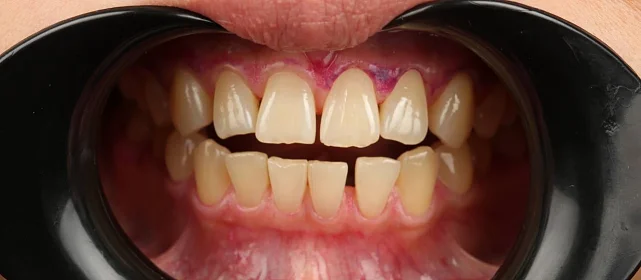

Нарушение соотношения челюстей и неправильное положение зубов — зубные ряды смыкались некорректно, зубы стояли со смещением.

Проблема: В клинику обратился мужчина с жалобами на неправильное положение зубов и смыкание — ряды сходились некорректно, зубы стояли со смещением. При этом было важно, чтобы лечение оставалось незаметным для окружающих, поэтому вариант с брекетами не рассматривался.